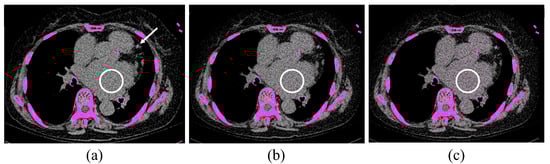

2. Materials and Methods

2.3. Image Analysis

2.4. Phantom Study

2.5. Calcium Scoring

3.1. Patient Study

3.2. Phantom Study